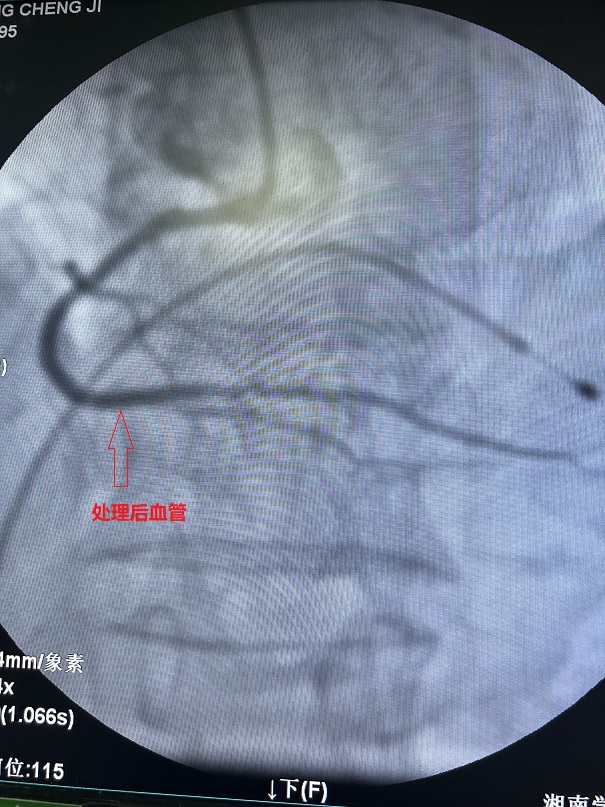

廖昆介绍,冠脉内斑块旋磨术是指将一个类似橄榄形的旋磨头送达钙化血管处,通过旋磨头的高速旋转,对冠脉钙化部位进行打磨,它能有效改变钙化斑块的顺应性,从而方便后续支架的置入。主要适用于解剖学上高危的病变,如钙化的病灶、开口处病灶、球囊难以扩张的病灶和长段血管病灶,尤其适用于钙化病灶。

凭借精湛的技术和充分的准备,王先生的病变血管,在术中得以顺利开通并成功置入支架,术后患者胸闷气促症状得到明显缓解。王先生及家人都对治疗效果非常满意。